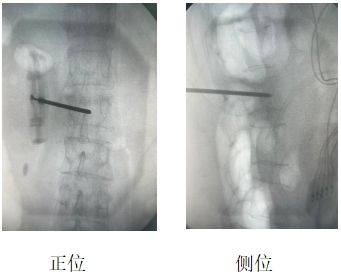

患者辛某(化名),女性,69岁,因“腰部剧烈疼痛伴活动受限2天”入院。既往有骨质疏松症病史,影像学检查提示L2椎体新鲜压缩性骨折,VAS评分8分。

当地医院建议外科手术治疗,患者及家属拒绝开刀手术,遂来我院疼痛科。结合患者自身情况,刘康主任与科室人员经讨论,决定行“经皮椎体成形术(PVP)”联合“脊神经后内侧支射频调控术”,同时解决椎体稳定性与神经源性疼痛问题。

刘康主任表示,椎体成形术+脊神经射频调控联合应用,较传统单一“骨水泥”植入对缓解疼痛有明显改善。

两者微创联合优势应用于“椎体压缩骨折”可单次麻醉、同一体位完成两项操作,降低手术风险,提升患者耐受性,显著缓解疼痛,大大减少“骨水泥”植入术后残余疼痛。 脊神经后内侧支射频是骨质疏松性压缩骨折(OVCFs)疼痛管理的重要补充。约30%患者“骨水泥”植入术后存在脊神经源性残留痛,联合射频可显著提升远期疗效。此病例为骨质疏松性骨折的个体化治疗提供了新思路。